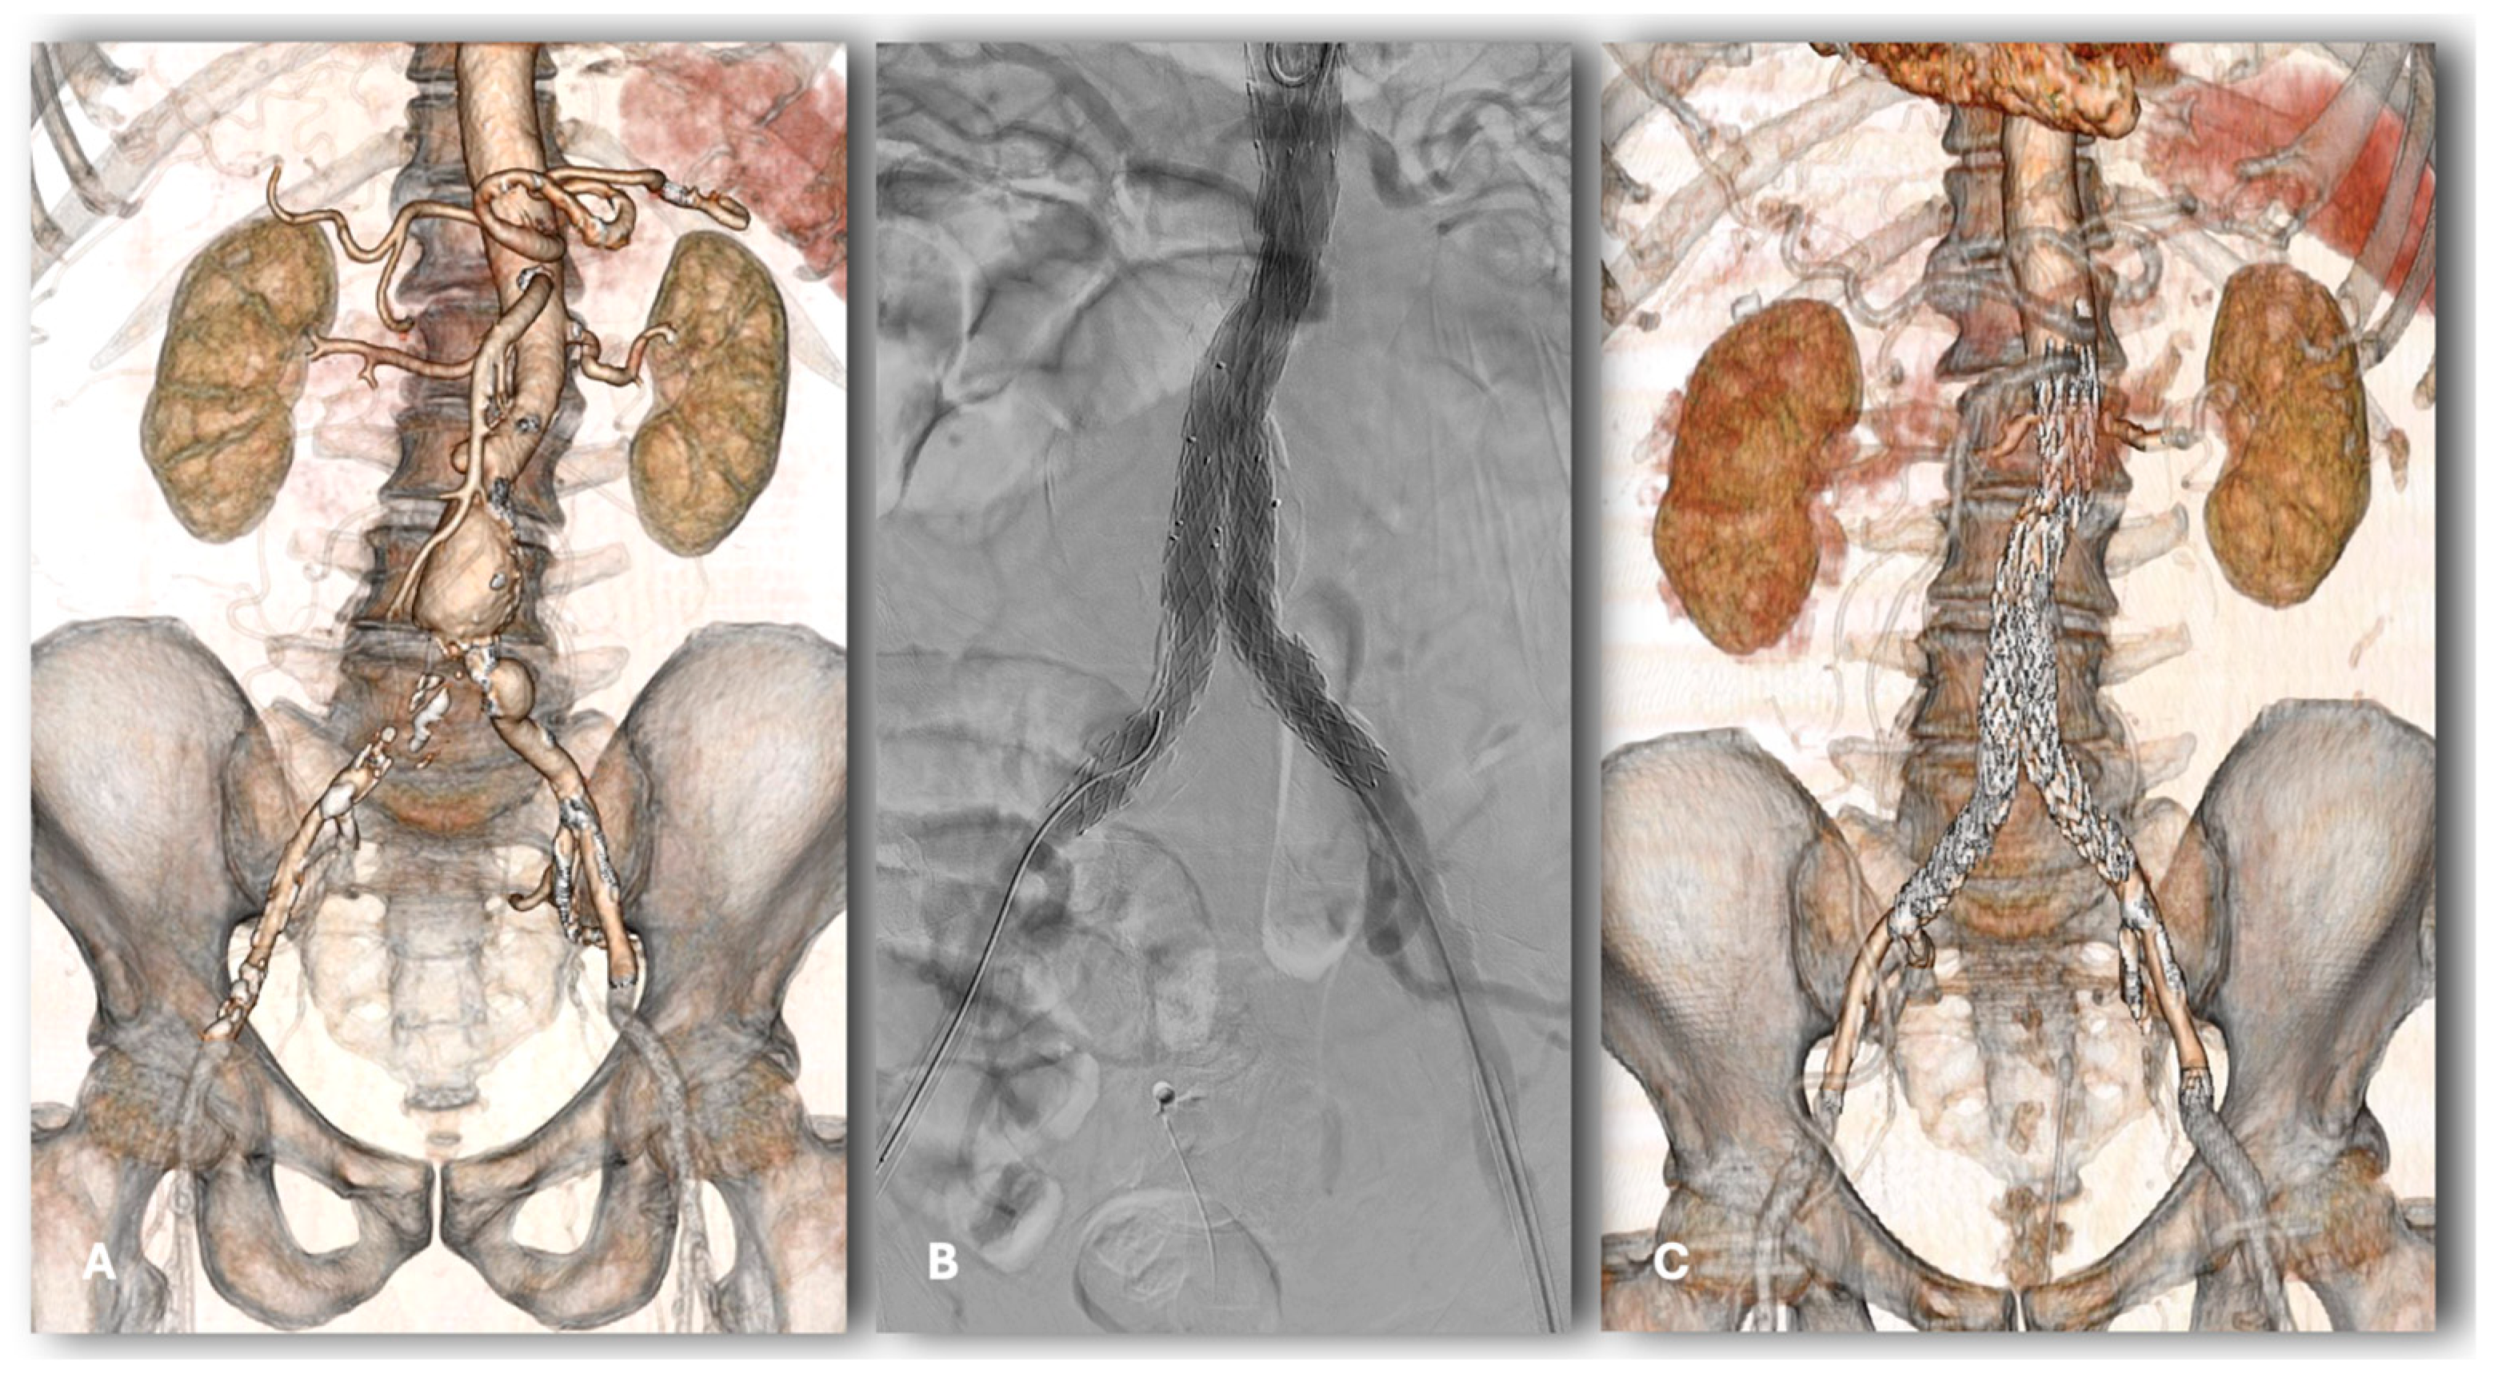

Early and Mid-Term Results of Endovascular Aneurysm Repair with the Cordis Incraft Ultra-Low Profile Endograft: A High-Volume Center Experience

Baccani, L.; Parlani, G.; Isernia, G.; Lenti, M.; Terpin, A.M.; Simonte, G. Early and Mid-Term Results of Endovascular Aneurysm Repair with the Cordis Incraft Ultra-Low Profile Endograft: A High-Volume Center Experience. J. Clin. Med. 2024, 13, 5413. https://doi.org/10.3390/jcm13185413